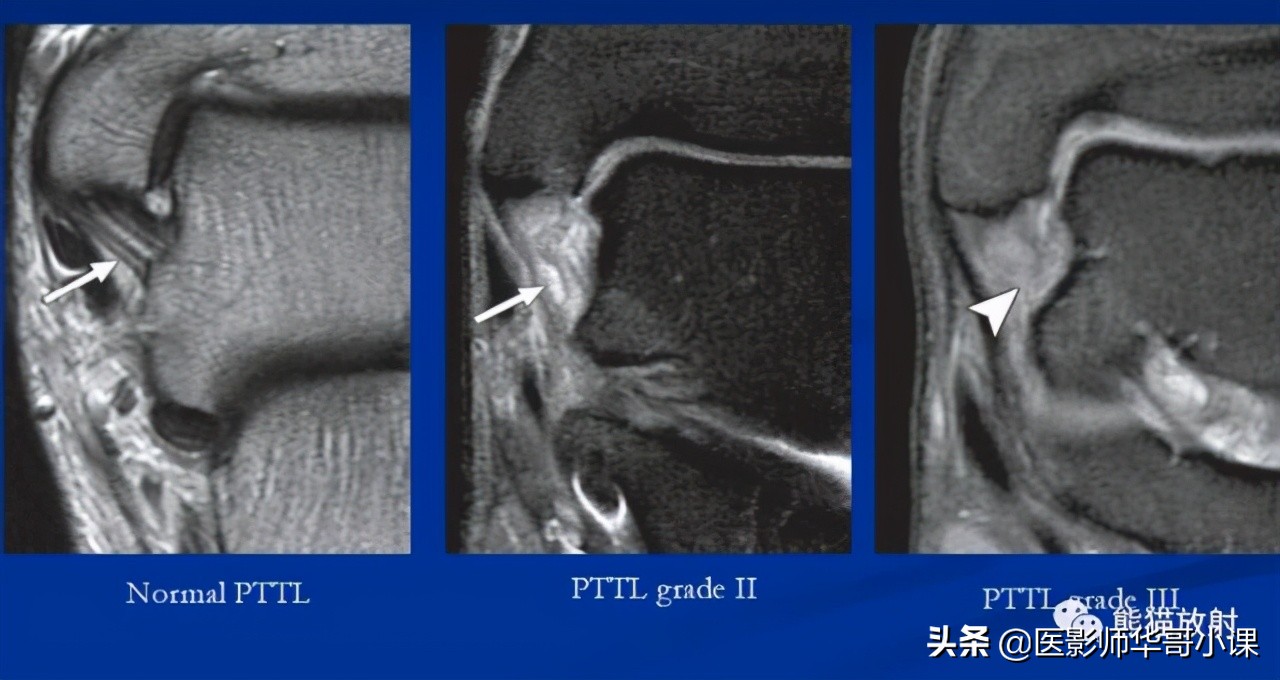

↓ 胫距后韧带损伤